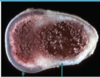

What is the lesion in this bone?

A

embolic osteomyelitis/suppurative osteomyelitis